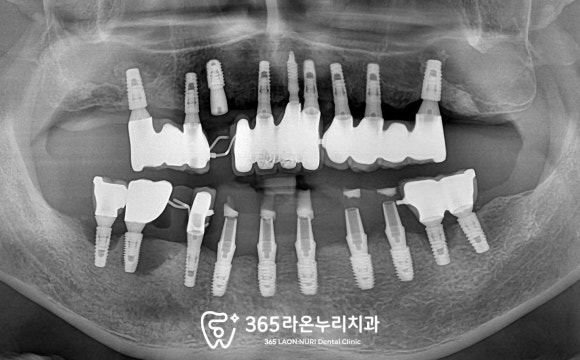

■ 4. 치료 과정

먼저 문제가 되던 #13은 발치 후

그 주변으로 뼈이식을 해두었습니다.

그리고 하악 역시 디지털 가이드를 제작하고

임시치아를 만들어드리기로 했는데요,

그렇게되면 기존의 플리퍼보다

고정력이 있어 사용하는데 훨씬

편하실 겁니다.

또한 직장 문제로 자주 내원이 어려우셨기에

내원 횟수 최소화를 위해

디지털 가이드를 이용하기로 했습니다.

디지털 가이드를 이용하면

하루에 여러 개의 픽스처를

심어드릴 수 있으니 말이죠.

이렇게 서지컬 가이드를 이용하여

계획을 마치고 나면

그 자리에 임플란트를 심게 되는데